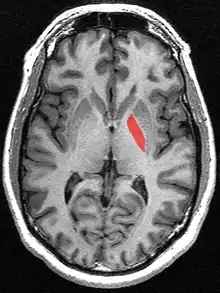

![]() Globus pallidus (in red) shown within the brain | |